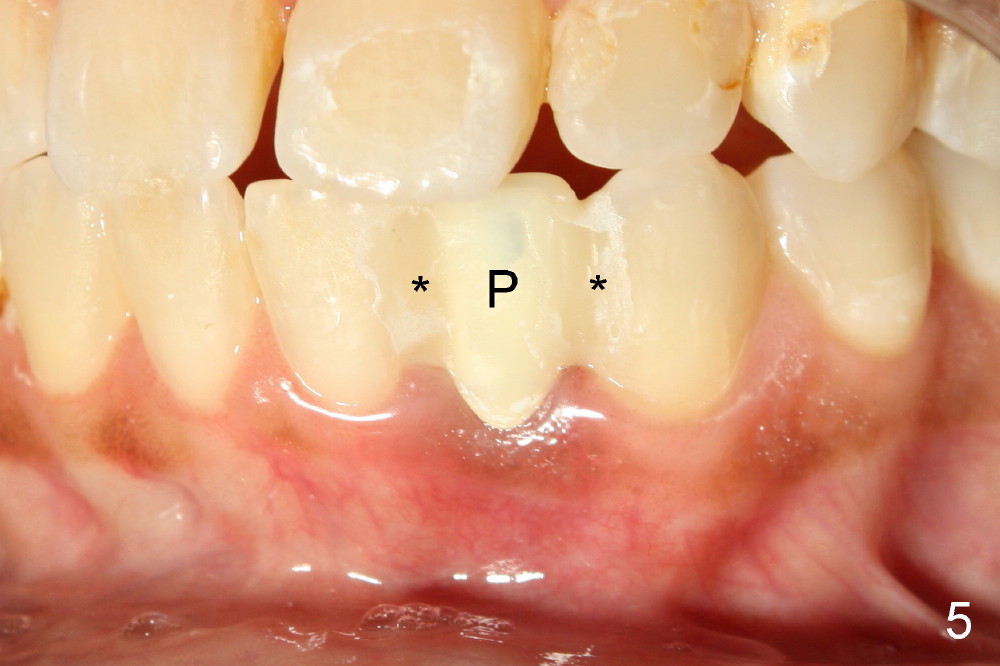

Informed consent is obtained with emphasis of potential damage to the neighboring roots.  Two PAs have to be taken with the first pilot drill (1.5 mm) in place for determination of initial trajectory (Fig.2,3).  Osteotomy is enlarged coronally with 2 mm pilot drill.  Finally a 3x17 mm one piece implant is placed with primary stability, determined tactilely (Fig.4).  Immediate provisional is fabricated.  To avoid micromovement, the immediate provisional (Fig.5 P) is bonded to the neighboring teeth with composite (*); it is further fixed in place with a lingual retainer (Fig.6 arrowhead).